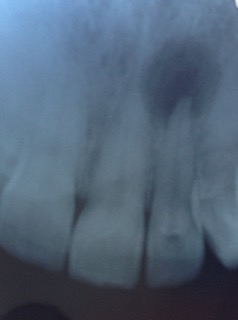

1. Simple Jaw Bone Infection. This sounds more serious than it actually is - BUT it still needs treatment! Here is a small X-ray of a tooth with an infection on the tip of the root. The infection shows up as the dark circular area at the top end of the tooth towards the right side of the image:

X ray of 3 front teeth, showing a black area around the root tip of the middle tooth.A root tip infection

And here's another one of a molar tooth with infection on the root tips - the dark shadows at the bottom ends of the roots of the middle tooth in the image:

An X ray of 2 molar teeth, with a black area around the roots of the molar on the right.infection on the double-rooted molar tooth

On the image above you can see that the tooth on the right-hand-side of the photo is smaller than the other 2 visible teeth. That's because it's a baby tooth (a "deciduous" molar). THAT MEANS that the patient here with the molar jaw bone infection is between 10 and 12 years of age! That's young, to be needing a molar root canal or an maybe the alternative is extraction.